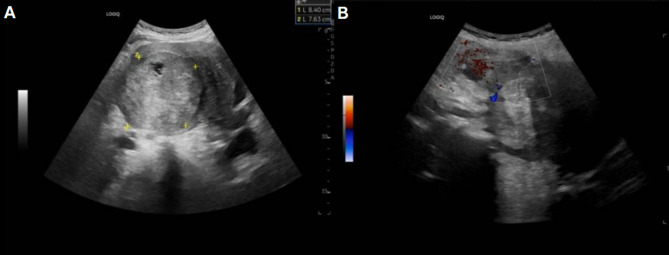

Case description: A 52-year-old woman presented at the clinic with right lower abdominal pain, persisting for over 5 days, significantly impacting her daily activities. Self-examination revealed a palpable abdominal mass. Ultrasonography identified an inhomogeneous echogenic mass within the uterus, initially suspected to be a uterine fibroid. Subsequent magnetic resonance imaging indicated uterine fibroids with tumor rupture and bleeding. The pathological assessment confirmed low-grade ESS. The patient underwent a total hysterectomy and double adnexectomy and is now 4 months postoperative and surviving well.